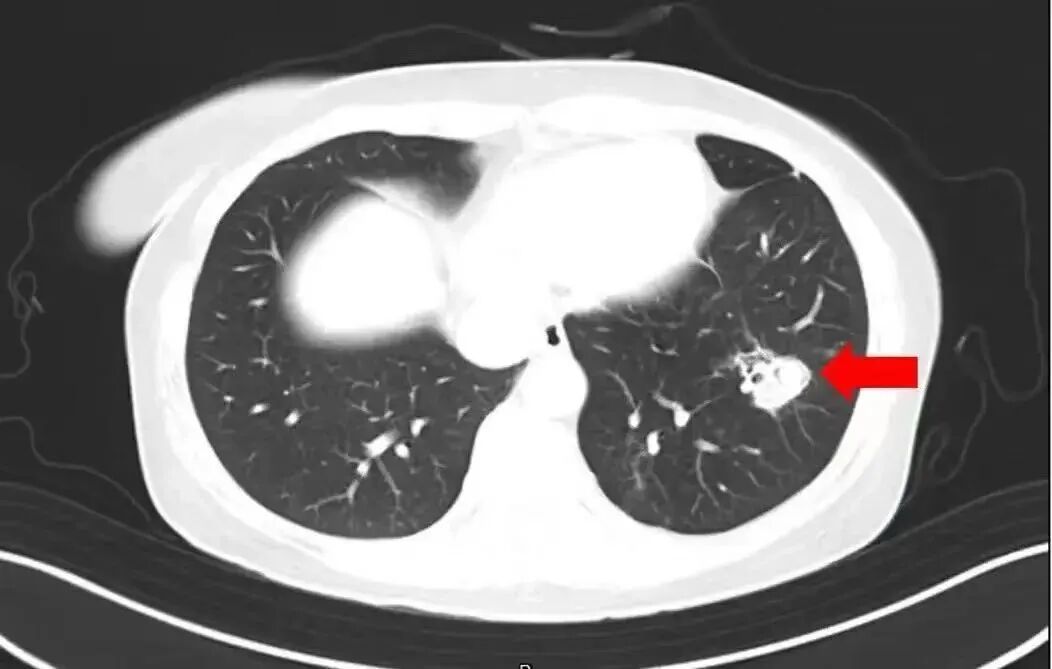

To further diagnose her condition, the doctor performed a fiber bronchoscopy and alveolar lavage fluid pathogen testing, and indeed found a large number of white fungal plaques on the airway walls, which were confirmed to be Aspergillus after testing.

Clinically, pulmonary aspergillosis is divided into invasive pulmonary aspergillosis, pulmonary aspergilloma, and tracheobronchial aspergillosis, with common symptoms including: persistent high fever that does not subside, which is difficult to alleviate with conventional antipyretics; worsening cough symptoms accompanied by chest pain and difficulty breathing; brownish or blood-streaked sputum; nasal congestion, purulent nasal discharge, and facial pain symptoms of sinusitis, which can lead to respiratory failure and even threaten life in severe cases.